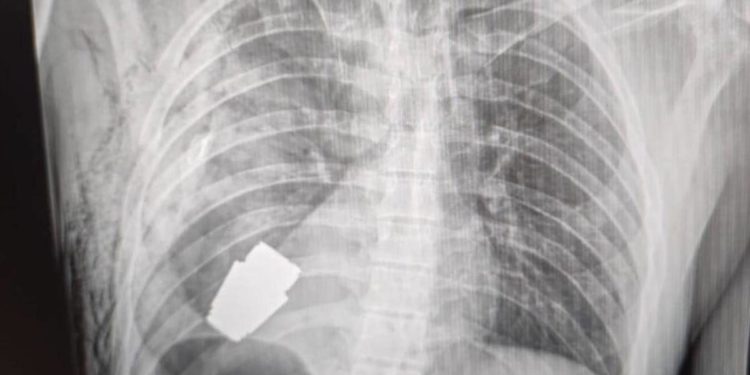

(Adnkronos) – Un’operazione per estrarre una granata non esplosa dal corpo di un soldato dell’Ucraina. Anton Gerashenko, consulente del ministero dell’Interno di Kiev, sui social pubblica la foto che documenta l’intervento eseguito dal chirurgo militare Andrii Verba. L’operazione, per estrarre la granata dal torace del militare, è stata effettuata alla presenza di due militari del genio, che in sala operatoria hanno guidato i medici per evitare che l’ordigno esplodesse.